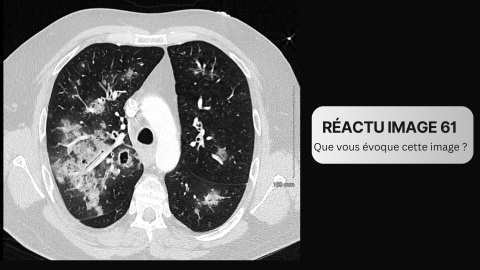

• Un infarctus cérébral de taille petite à étendue, définie par un score ASPECTS 3-10. Il s’agit d’un score radiologique évaluant la taille d’un AVC du territoire de l’artère cérébrale moyenne à partir d’une TDM cérébrale non injectée [3].

• Le protocole de l’étude n’a pas inclus d'analyse d'imagerie, et il n'est pas possible de savoir si le gain de survie identifié sous corticoïdes est lié à une réduction du volume de l'infarctus, une réduction de l’œdème, ou à un effet systémique autre.